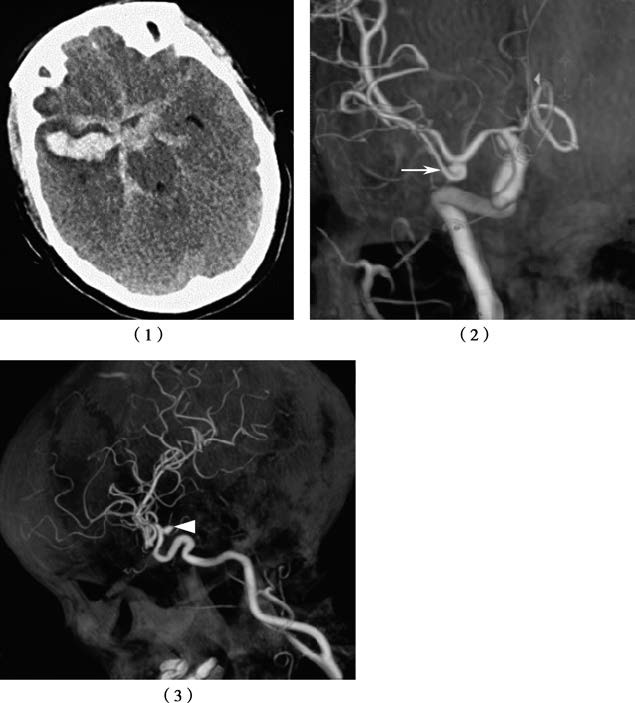

Figure 1 Multiple aneurysms with subarachnoid hemorrhage

1, CT shows subarachnoid hemorrhage, with severe involvement in the right Sylvian fissure.

2, The right middle cerebral artery aneurysm is identified as the culprit aneurysm causing the hemorrhage.

3, The right internal carotid artery aneurysm is also observed.